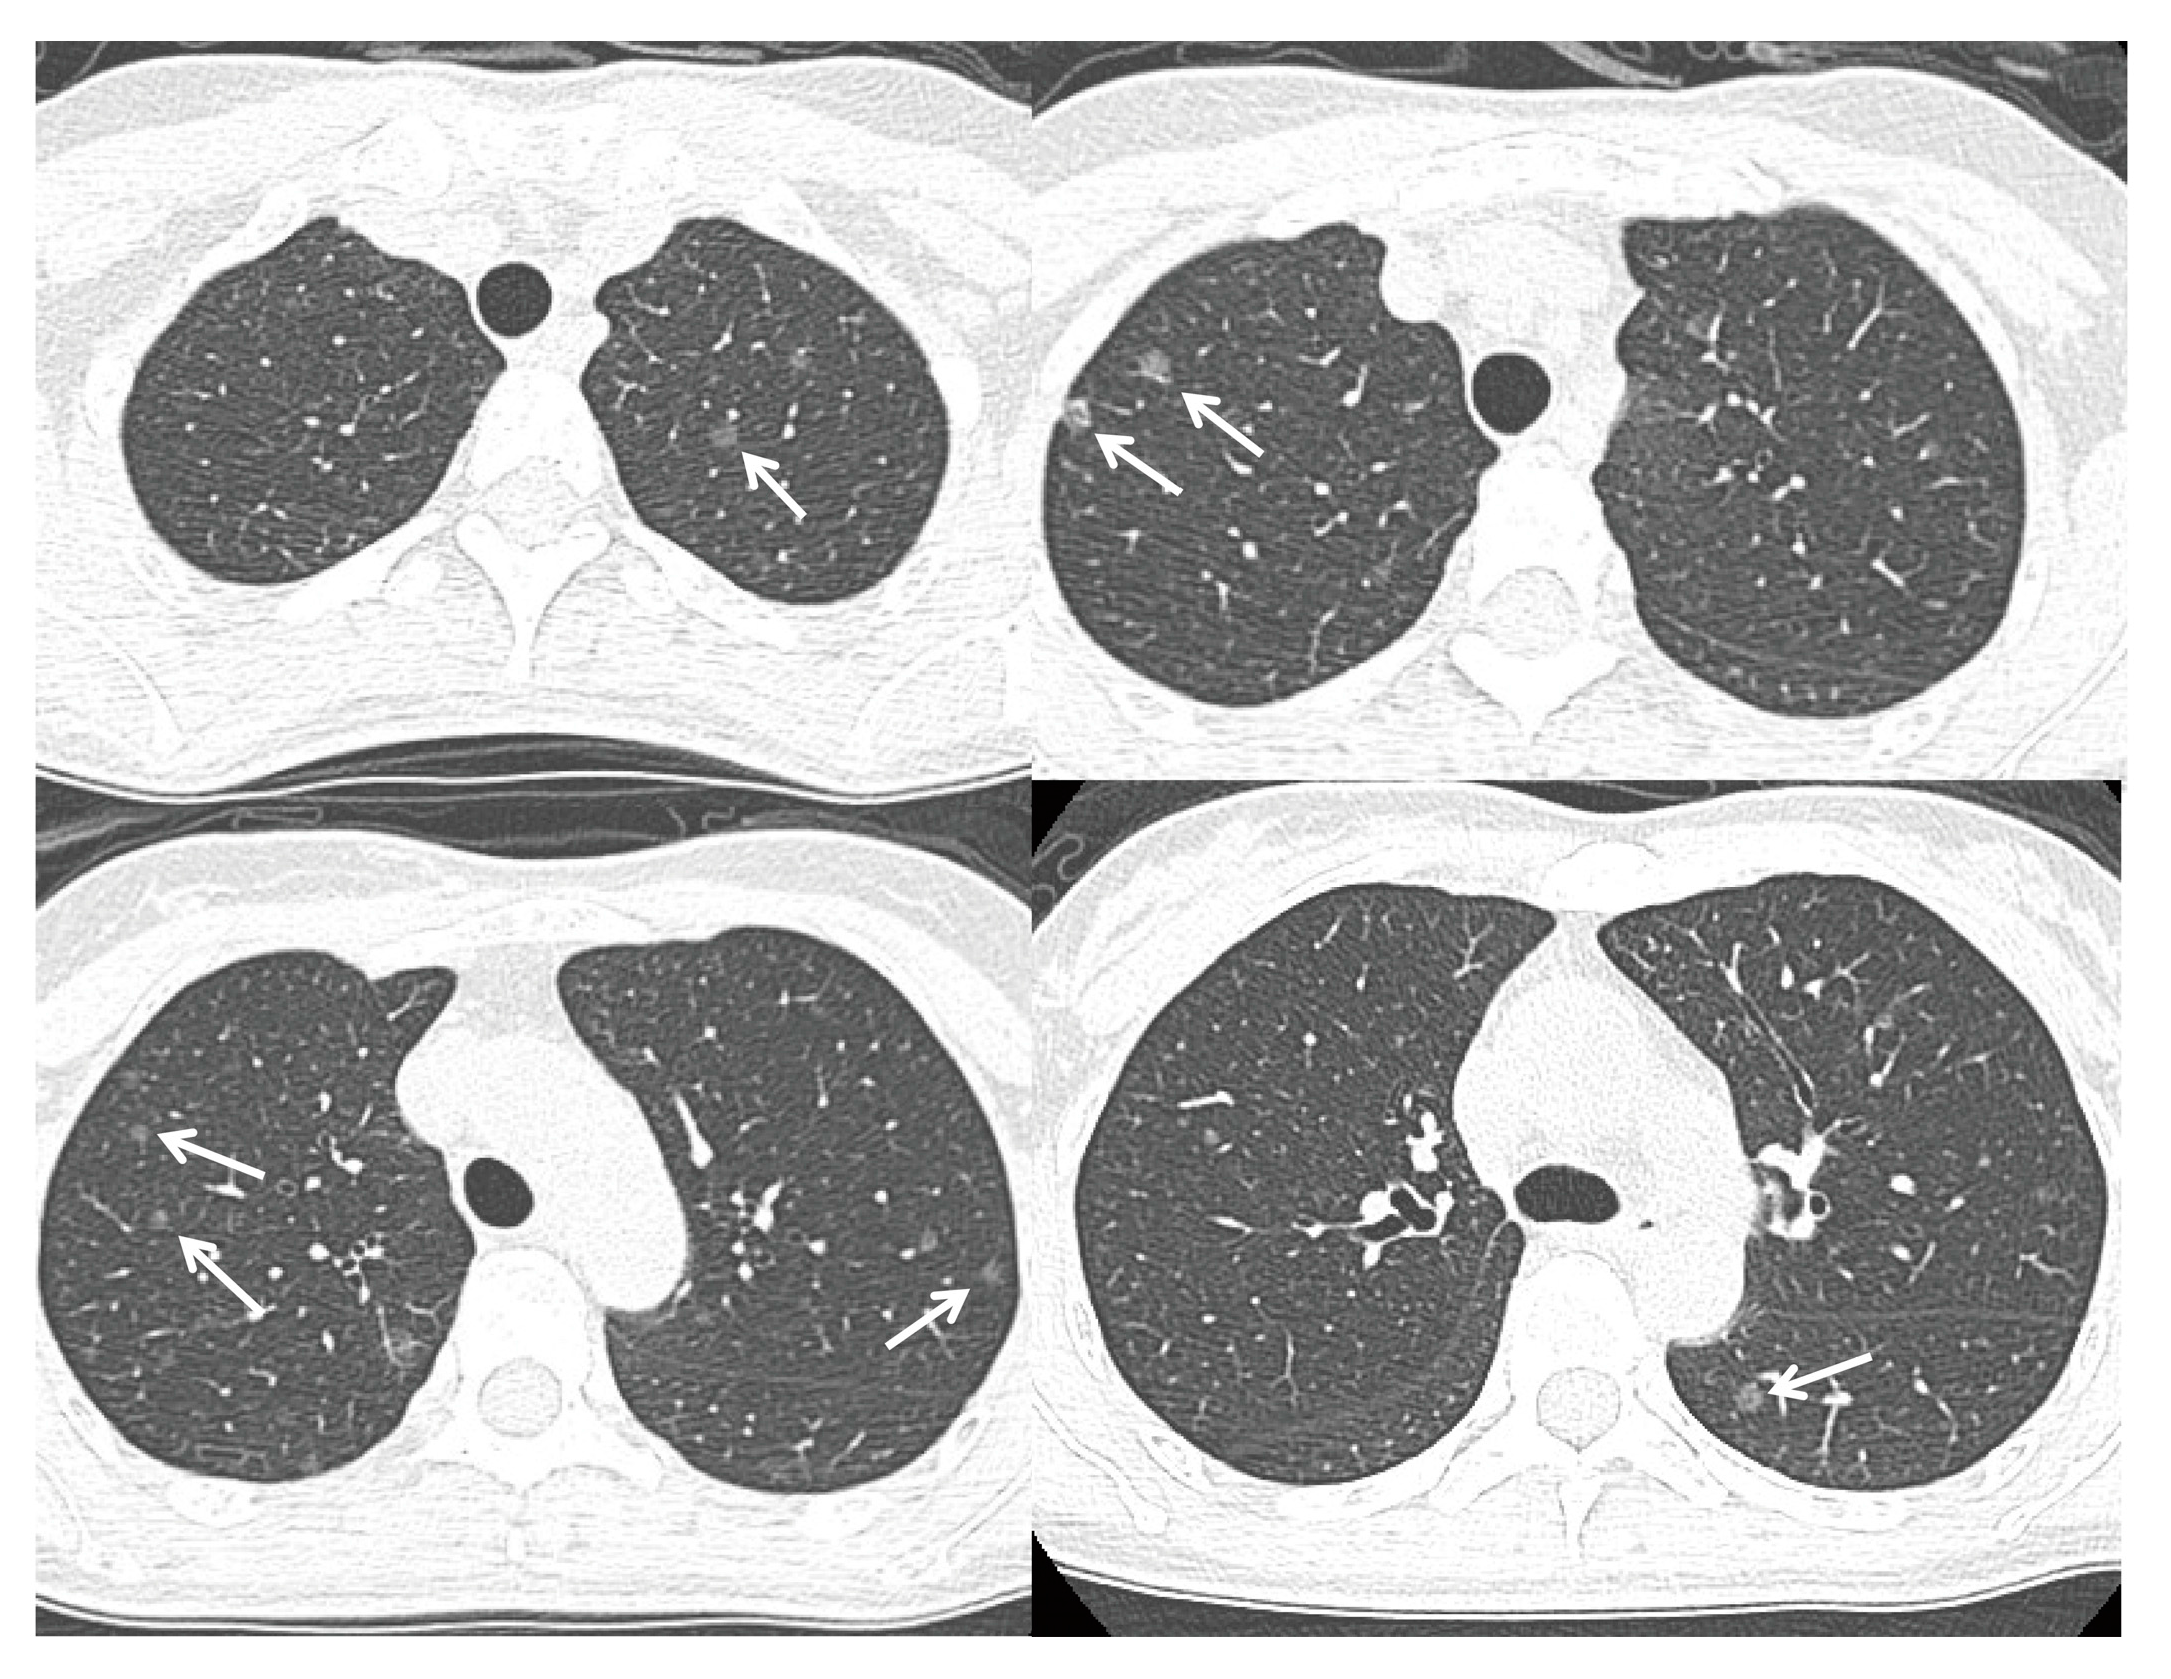

4. ER as Targets for Lung Cancer Therapy and Relationship with EGFR